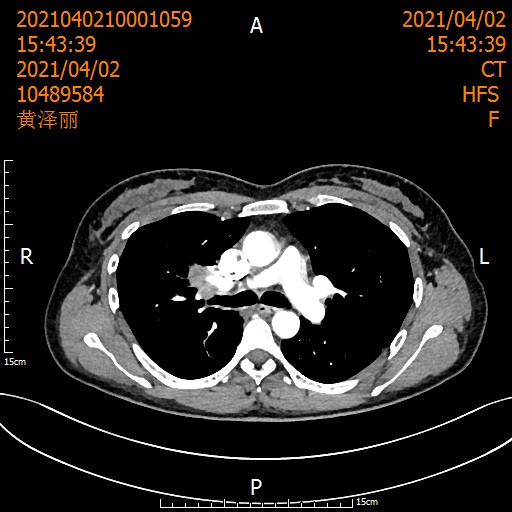

2021年,一位40岁的母亲因"咳血三月"到西南医科大学附属中医医院胸心外科就诊。CT结果显示:右上肺门区肿块,支气管粘液栓。活检确诊为非小细胞肺癌(T3NxM0)。

患者术前影像